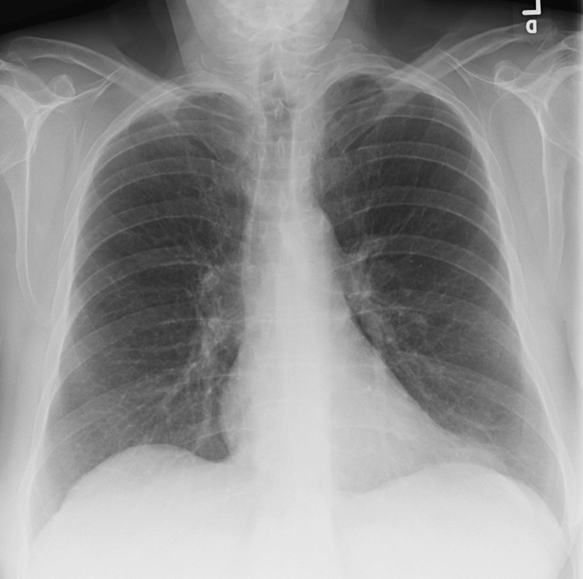

What Is Density On Chest X Ray Mean . Note there is a range of greyness,. Lung fields appear dark because of air. In combination with clinical information, each of these patterns is often helpful in reaching a diagnosis. In fact every radiologst should be an expert in chest film. Here are the four natural tissue densities seen on a chest radiograph. By christopher pavlinec, md — last updated: Fortunately, chest ct can be done to. Hilar enlargement may be unilateral or bilateral, symmetrical or asymmetrical.